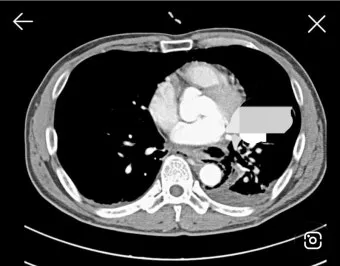

3단계, 흉부 초음파·CT 검사입니다.

특히 초음파는 수십 mL 수준의 적은 양 흉수도 찾아내는 데 도움이 되고, 어디에 얼마나 모여 있는지를 파악해 나중에 흉강천자(물을 뽑는 시술)를 할 위치를 잡는 데 쓰입니다.:contentReference[oaicite:22]{index=22}

4단계, 흉강천자(흉수 검사 및 배액)입니다.

국소마취를 하고 바늘이나 가는 관을 통해 흉막 사이에 고인 액체를 일부 또는 상당량 뽑아내면서, 단백질·당·염증수치·암세포 유무 등을 검사해 여출성인지 삼출성인지, 감염성인지 악성인지 등을 감별합니다.:contentReference[oaicite:23]{index=23}